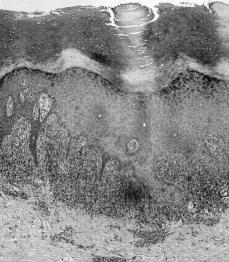

Una mujer de 32 años, peluquera de profesión, sin antecedentes médicos ni quirúrgicos de interés, consultó en nuestro Servicio en agosto de 1997 por la aparición de unas lesiones muy pruriginosas que se habían iniciado 3 meses antes en las palmas de ambas manos y en las plantas de ambos pies, sin otras lesiones aparentes en el resto de la piel. No había tenido ningún episodio de estrés psíquico. En el momento de comenzar su erupción no estaba tomando fármaco alguno. Las lesiones las estaba tratando con Positón® pomada y cetirizina oral. En la exploración dermatológica se apreciaron en palmas y plantas dos tipos de lesiones: unas eran pápulas hiperqueratósicas, duras, de color amarillento, y las otras, pápulas violáceas, aplanadas, poligonales, con collarete descamativo periférico (Fig. 1). En arco plantar y en superficie palmar de muñecas esas lesiones adquirían un aspecto liquenoide franco, con evidentes estrías de Wickham. No existían lesiones fuera de las zonas mencionadas, en especial en las mucosas genital ni oral.

FIG. 1.--Aspecto clínico de las lesiones agrupadas en arco plantar con pápulas de diferente morfología.